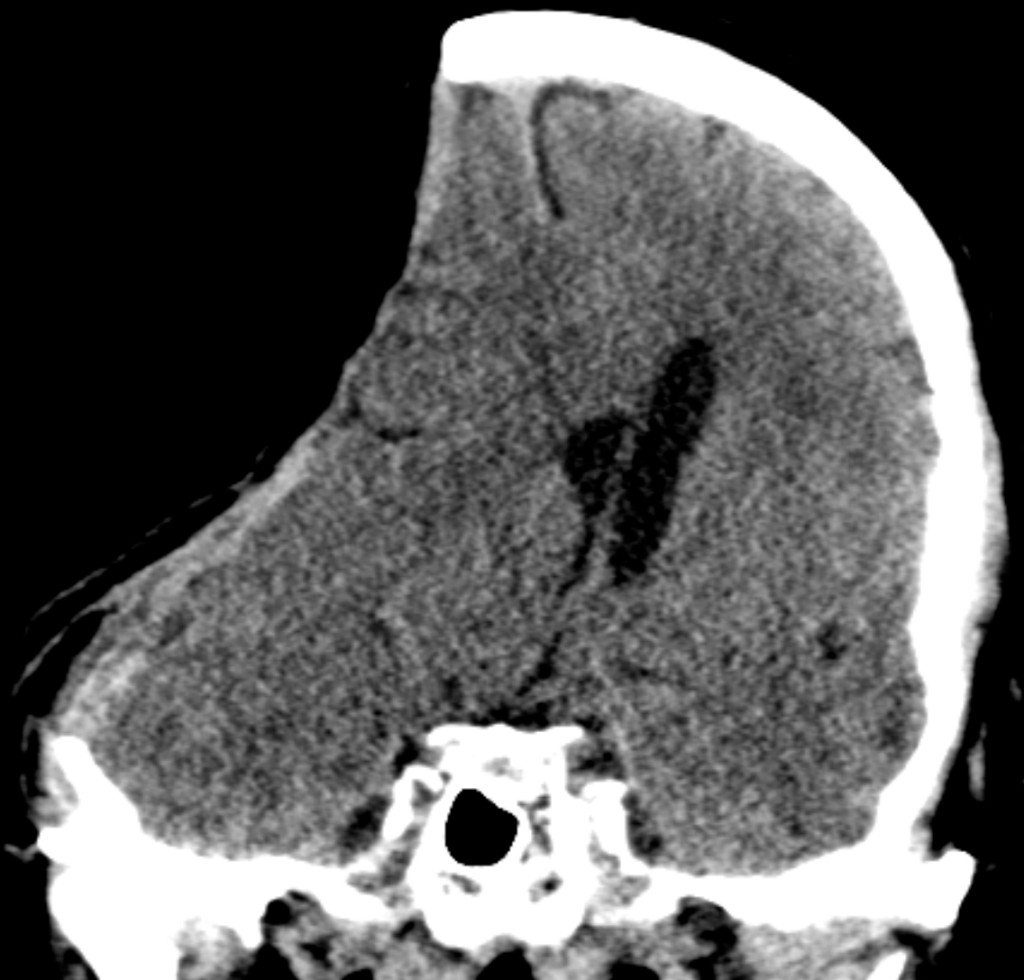

Bildet viser paradoksal hjerneherniering hos en pasient med kjent nyresvikt, hypertensjon og koronarsykdom som noen måneder tidligere hadde gjennomgått hemikraniektomi. Paradoksal hjerneherniering er en sjelden komplikasjon etter fjerning av en større del av hodeskallen og er potensielt livstruende. En av hodeskallens oppgaver er å beskytte hjernen mot relative trykkforskjeller mellom det intrakranielle og det atmosfæriske trykket. Ved større kraniektomier kan det atmosfæriske trykket overstige det intrakranielle trykket og gi forskyvning av underliggende hjernevev og i verste fall herniering (1). Tilstanden ses oftest ved akutt oppståtte trykkendringer etter lumbalpunksjon eller drenasje av cerebrospinalvæske (shuntbehandling eller ventrikkeldren) hos kraniektomerte pasienter, og kan forverres ytterligere av dehydrering eller elevert leie. Akuttbehandlingen er leieendring med senket hodeende og bedring av eventuelle mekaniske forhold ved cerebrospinalvæskedrenasje (justering av motstand på ventrikkel- eller lumbaldren) samt tilbakelegging av benlappen dersom det er mulig. Intensivbehandling med overtrykksventilasjon (2) og væske- eller sviktbehandling kan medføre endrede intrakranielle trykkforhold og i noen tilfeller bidra til utvikling av tilstanden.